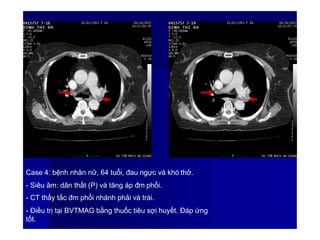

Case 4: bệnh nhân nữ, 64 tuổi, đau ngực và khó thở.

- Siêu âm: dãn thất (P) và tăng áp đm phổi.

- CT thấy tắc đm phổi nhánh phải và trái.

- Điều trị tại BVTMAG bằng thuốc tiêu sợi huyết. Đáp ứng

tốt.